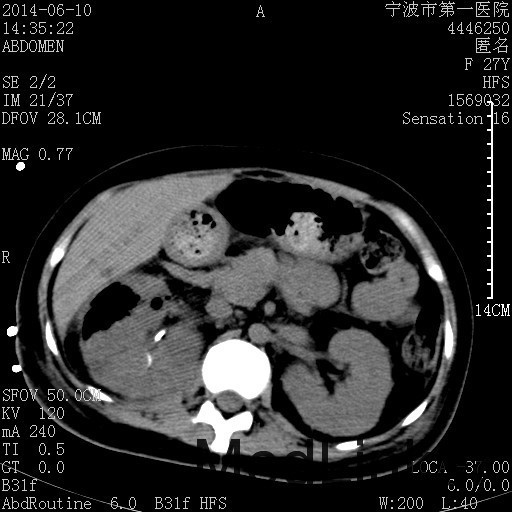

诊断为“气性肾盂肾炎,感染性休克,糖尿病酮症酸中毒” 血、尿、脓液培养均示“克雷伯杆菌” 入院第2天行“右双J管置入术” 入院第3天、7天行“右肾穿刺造瘘术” 入院1月行“右肾切除术” 术后顺利康复出院。

气性肾盂肾炎 • 气性肾盂肾炎是产气尿路病原体引起的急性肾实质坏死和肾周感染 • 大肠杆菌是最常见的病原菌,其次是克雷伯杆菌和变形杆菌 • 绝大多数气性肾盂肾炎患者合并糖尿病 • 死亡率19%至43%,单独的内科治疗通常是致命的,大部分患者最终需要行肾切除术 下一步治疗方案 • 拟行右肾切除术 • 患者经充分引流、抗感染治疗后现病情平稳,血糖控制良好 • 感染灶范围大,不能通过保守治疗消除,以往经验告诉我们保守治疗效果往往不佳 • 长期抗生素应用易引起真菌感染、伪膜性肠炎等并发症 • 若细菌对泰能耐药,后续抗感染治疗将十分困难 术前评估 • 手术风险评估(NNIS分级 2~3分) – IV 类手术切口(1分) – P3有严重系统性疾病,日常活动受限,但未丧失工作能力(1分) – T1手术在3小时内完成(0~1分) – 营养危险评分(NRS-2002) 营养状态评分3分+疾病严重程度评分2分=5分 围手术期治疗 • 术前、术中、术后血糖控制和调整 • 术后重症监护支持 • 感染控制和抗生素使用 • 手术前麻醉准备 患者最终在入院后1月行右肾切除术,术后康复出院。